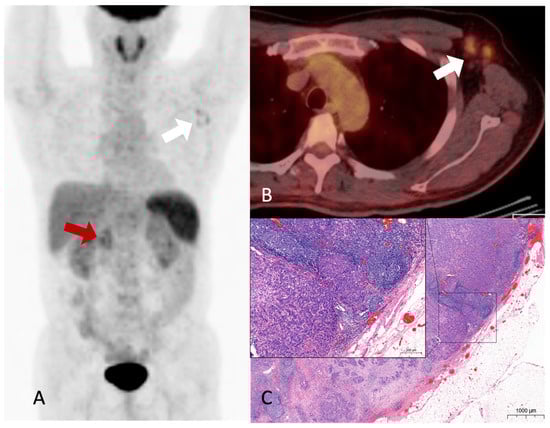

Hypermetabolic nodular activities are noted in the common bile duct and duodenopancreatic area (A, red arrow), and left axillary area (A, white arrow) on the maximal-intensity projection image of the 18F-FDG PET/CT. Hypermetabolic enlarged lymph nodes are noted in the fusion axial image (B, white arrow). No abnormal hypermetabolic activity was observed in the liver or lungs. Although diffuse uptake was observed in the spleen, no specific abnormalities were detected on contrast-enhanced abdominal CT and MRI imaging. This finding was presumed to be related to the patient’s underlying anemia, and it required further confirmation during follow-up. Furthermore, there was no evidence of splenic metastasis during follow-up. Moderately hypermetabolic lymph nodes in the left axillary area were difficult to exclude metastasis completely. An excisional biopsy of the axillary lymph nodes was performed because the treatment was changed from surgery to systemic therapy based on the presence or absence of distant metastases. Histological reports revealed the presence of adenocarcinoma, which was consistent with metastasis from CBD cancer. An H&E-stained slide of the axillary lymph node showing metastatic carcinoma (C). Accordingly, the patient’s treatment plan was modified; further, gemcitabine, cisplatin, and paclitaxel regimens were administered, resulting in a partial response with good performance. Subsequently, a surgical procedure (a pylorus-preserving pancreaticoduodenectomy) was performed. The patient survived for 2 years and 1 month after the diagnosis. Although there have been recurrences after surgery, the patient is currently maintaining a stable status through palliative chemotherapy. Metastasis is a hallmark of cancer and the leading cause of cancer-related death. Although many advances have been made in understanding metastasis, it is not yet fully understood [1]. The liver is the most common (11.9–23.2%) distant metastatic site of extrahepatic bile duct cancer, and metastases are known to be diagnosed in the lung, distant lymph nodes, bone, or brain [2]. Distant metastasis to the axillary lymph nodes from the primary tumor in the abdomen is rare. In particular, it is rarely discovered at the time of diagnosis except in cases with extensive lymph node metastasis to the abdomen or distant metastasis to other organs [3]. The case of recurrence due to axillary metastasis during post-operative follow-up is also very rare, thereby warranting a case report [4]. One case has been reported in which a patient with metastases to the abdominal and axillary lymph nodes, for whom the primary cancer origin could not be identified, was diagnosed with intrahepatic cholangiocarcinoma through a postmortem examination [5]. As with any type of cancer, accurate staging is essential for the selection of an appropriate treatment and a favorable prognosis. If distant metastases are not recognized and local treatment is performed, especially in patients being considered for surgery based on suspected primary tumor and regional lymph node involvement, appropriate treatment is delayed, and the patient’s prognosis is inevitably poor. In the current patient, surgical treatment was feasible only when an abdominal CT scan and MRI were initially performed. However, following the 18F-FDG PET/CT scan, axillary lymph node metastasis was suspected, leading to the confirmation of distant metastasis through tissue examination. As a result, the treatment approach shifted to systemic therapy, and the patient responded to the treatment. 18F-FDG PET/CT is known to effectively diagnose distant metastases in various cancers [6], and many reported cases have highlighted its ability to detect metastases in unexpected locations [7,8,9]. A previous study showed that for approximately 15% of patients with suspected and potentially operable cholangiocarcinoma, treatment altered with 18F-FDG PET/CT scans [10]. However, there have been no reported cases of axillary lymph node metastasis without other distant metastases identified during the staging process in patients with CBD cancer who are being considered for surgery. Herein, we emphasize the importance of determining treatment through an accurate diagnosis before surgery, elucidating a case in which unexpected distant axillary lymph node metastasis was discovered following 18F-FDG PET/CT in a patient with extrahepatic cholangiocarcinoma who was scheduled for surgery.